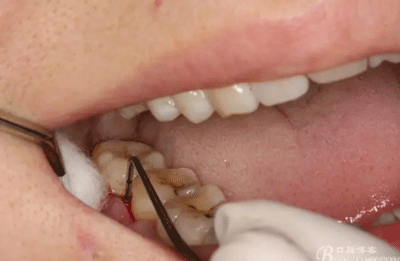

圖4.術(shù)前47遠(yuǎn)中探針檢查,遠(yuǎn)中牙周袋8mm